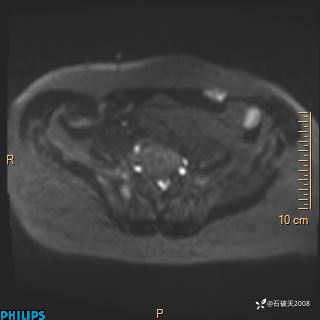

2023年3月份MRI影像

DWI

现病史:7个月前患者因骶尾部占位就诊于北京大学人民医院,MRI示:骶骨右侧及右骶前占位,考虑骨巨细胞瘤可能,动脉瘤样骨囊肿可能,神经源性肿瘤待排。行手术治疗,术后病理回示:XXXXX。术后给予对症治疗,具体不详,恢复良好。近几个月反复出现发热,伴骶尾部不适,多次住院给予对症治疗,2天前患者无明显诱因再次发热伴骶尾部不适,无大小便失禁,为求进一步治疗,遂门诊来我院,在门诊初步检查后,以“骶尾部肿物”为诊断收入我科。入院来患者神志清,精神一般,饮食睡眠可,大小便无明显异常,体重无下降。